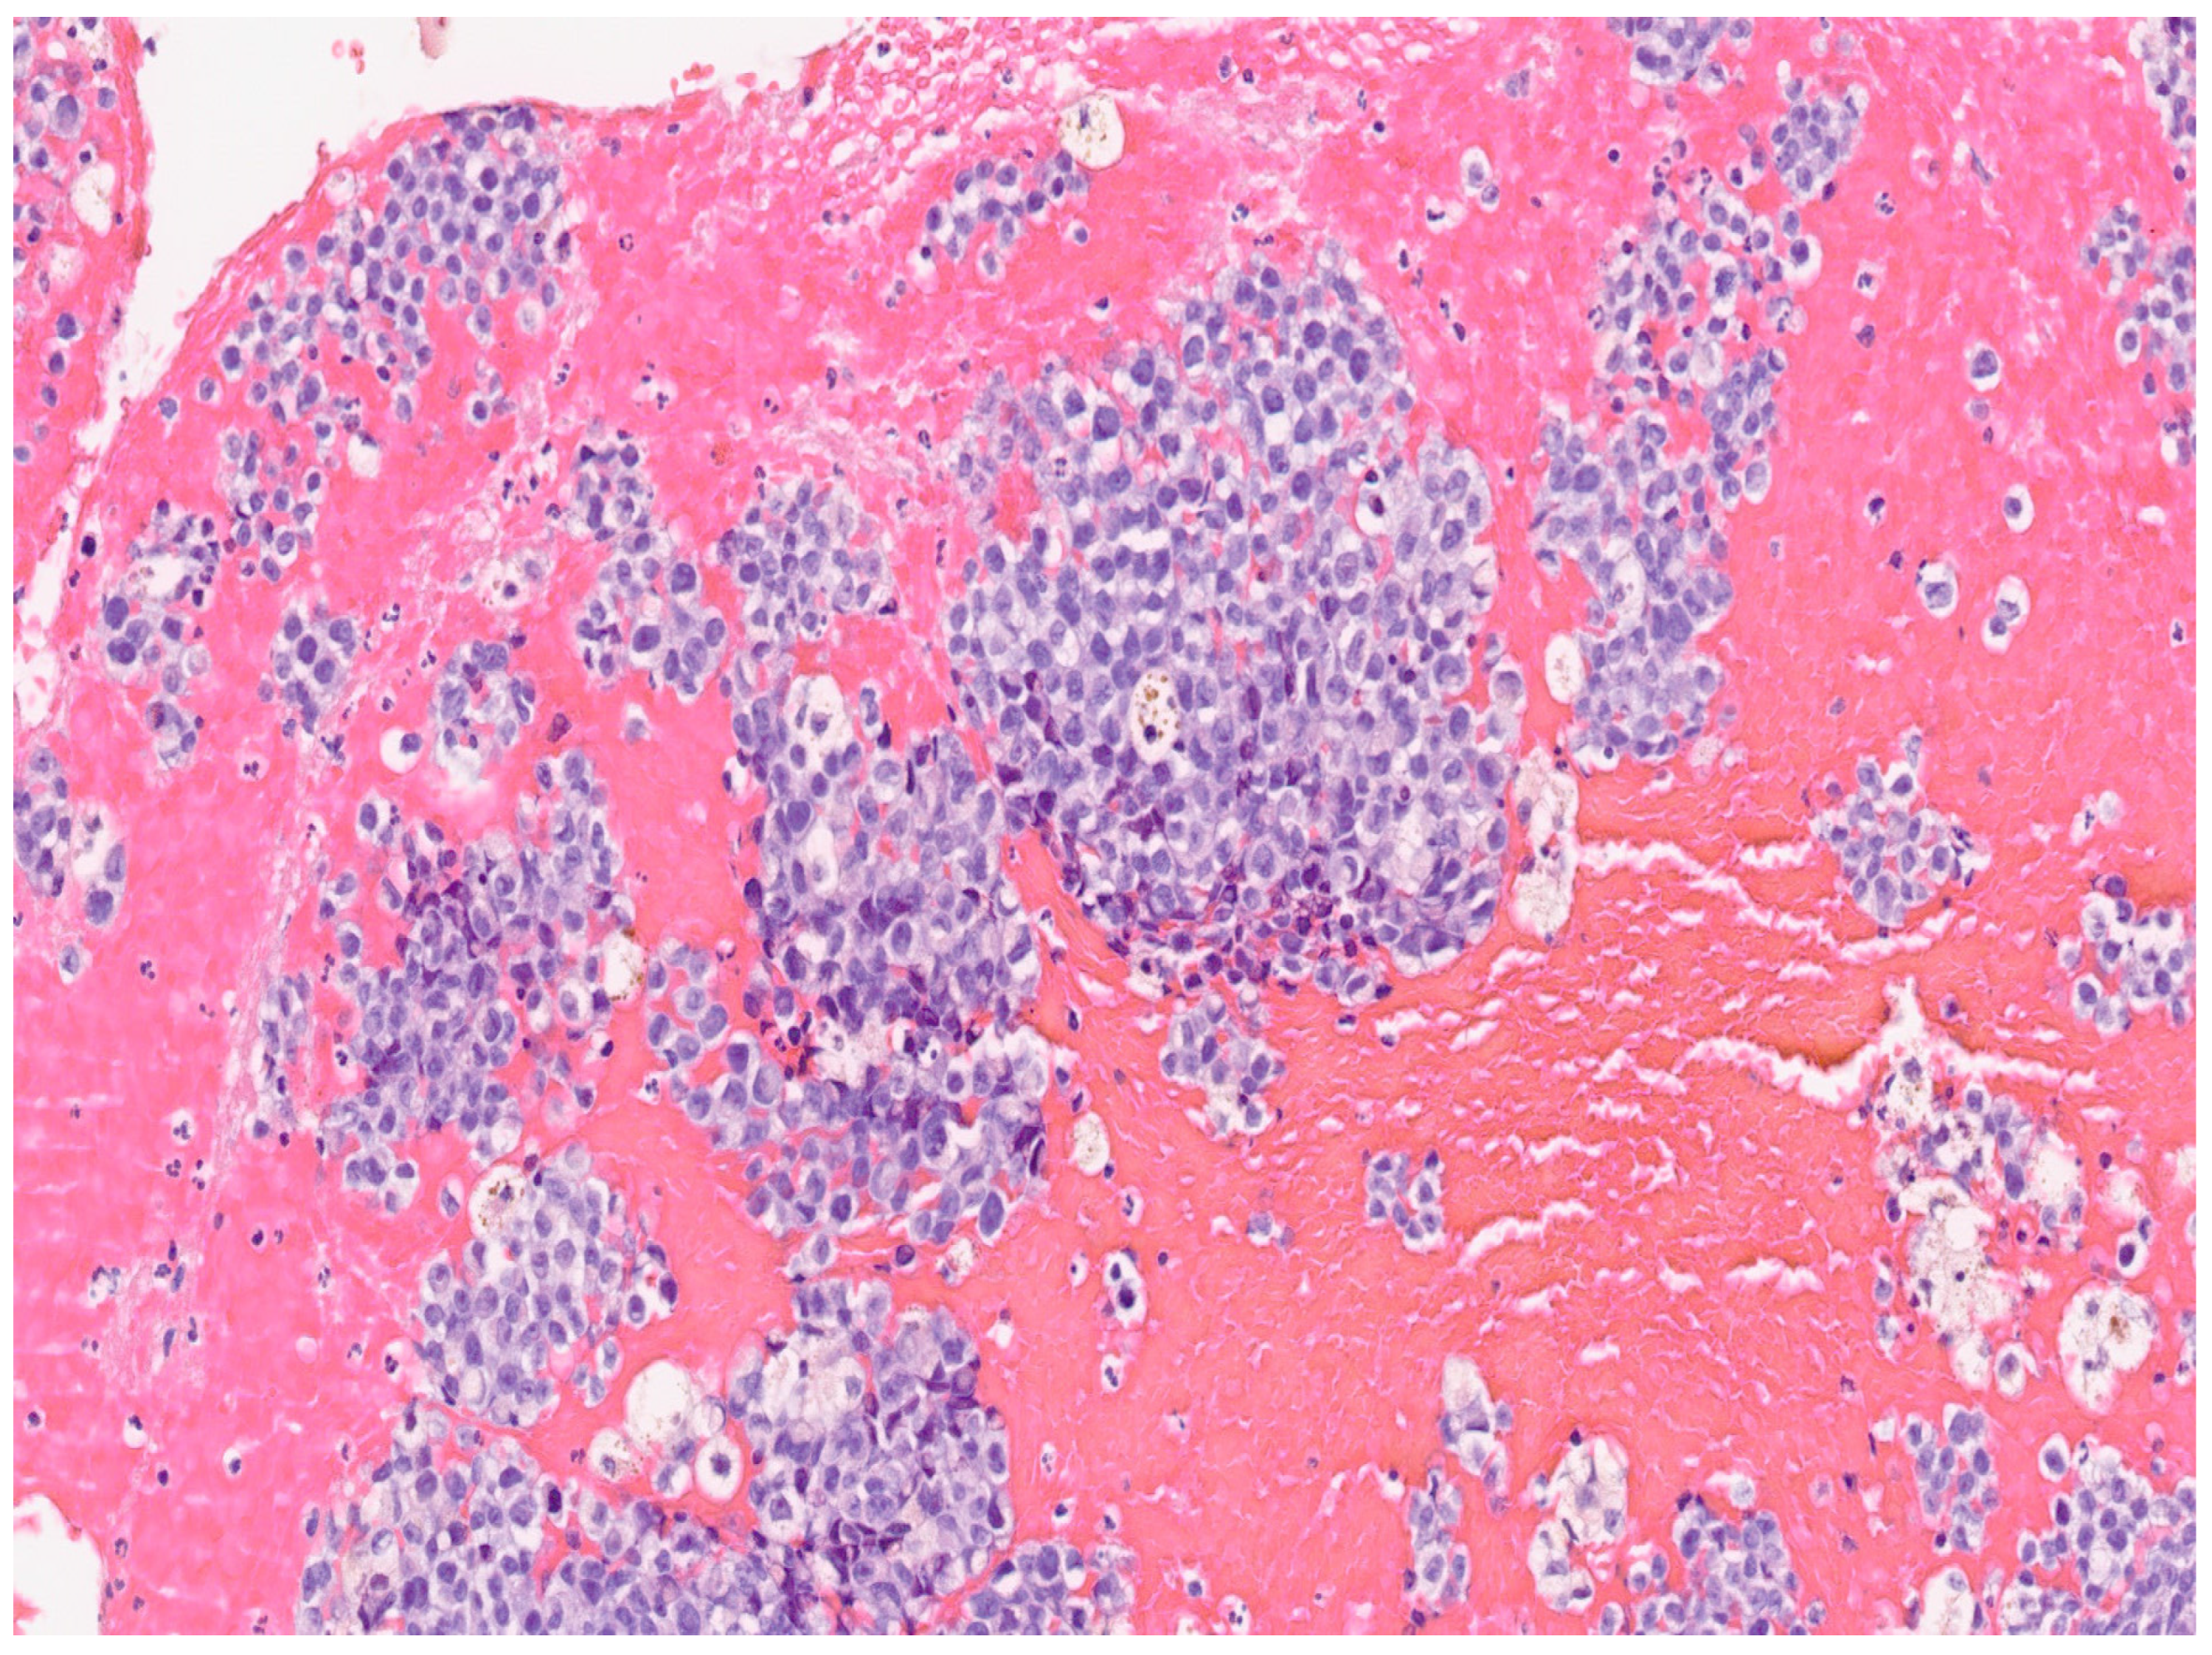

3. Results